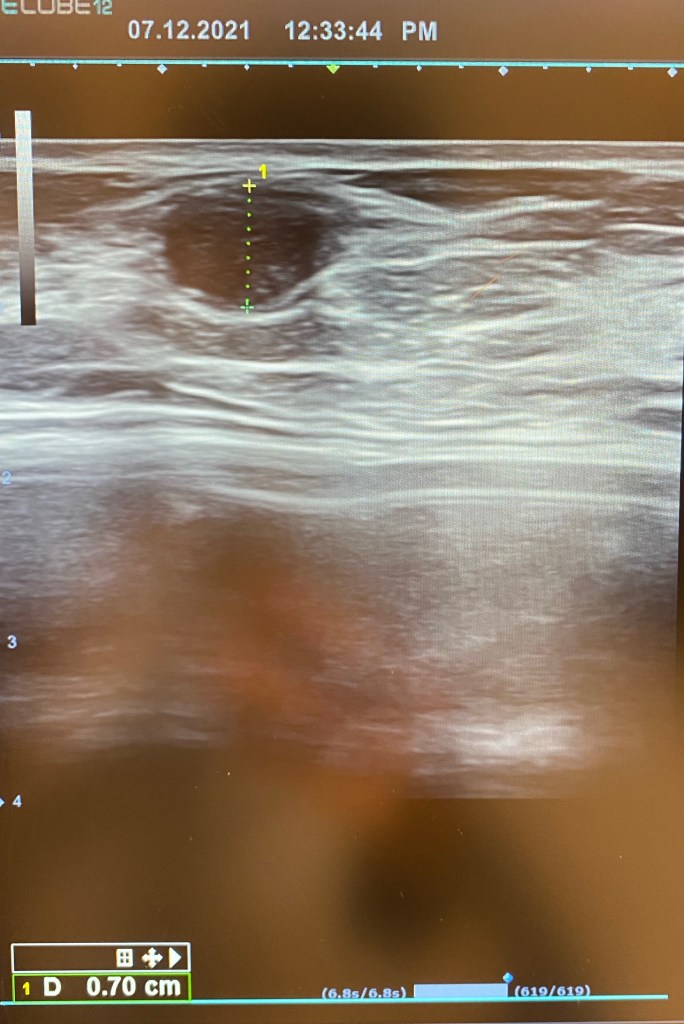

The doctor in my home town wasn’t able to diagnose the lump just from the scan as it looked dodgy, so they had to send me to another hospital 5 hours away by train.. my mom came with me. And I went to see another doctor that specializes in breast/ mammography / radio frequency department at the hospital in Bodø. At the end of the day He sent the lump for analysis. I was so scared and nervous waiting for answers days after.

The same day when I travelled back to Dubai I got my tests results and turned out it was a tumor, a tumor in the fibroalgenoma family and it was not cancerous. I was so relieved and grateful that I looked it up when I did.